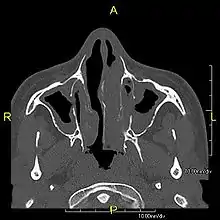

Axial CT image showing chronic sinusitis in an individual with Kartagener syndrome

When accompanied by the combination of situs inversus (reversal of the internal organs), chronic sinusitis, and bronchiectasis, it is known as Kartagener syndrome[3] (only 50% of primary ciliary dyskinesia cases include situs inversus).[11]